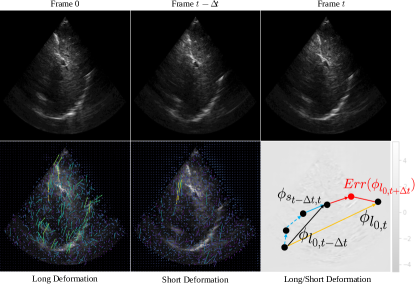

Refer to caption

Figure 6: Qualitative comparison of different baseline models and the proposed LSDM by tracking validation on the CLUST2D training set. We select a representative dataset entry to demonstrate LSDM superior tracking performance. We show the start frame at frame 0 (top-left), landmark center coordinate tracklet comparison (top-right) and selected frames with landmark tracking results (bottom). We can observe a stable and accurate tracking performance of LSDM, while other baselines fail at accumulating tracking error through the whole sequence. Supplementary V summarizes other tracking results and their visualization. Best viewed in color.

LSDM achieves accurate tracking by learning an optimized deformation between the exemplar and follow-up instances, which can help the downstream tracking network for finding the best candidate with plausible deformation. As shown in Table I, LSDM outperforms several baselines. Traditional correlation filtering based methods such as KCF and LCT cannot achieve satisfactory tracking performance on large-scale datasets due to various challenges. Even though methods like LCT incorporate historical information for updating tracking kernels, these baselines cannot produce accurate tracklets, lacking high-dimensional representation. Compared with tracking methods based on siamese networks such as SiamFC and SiamRPN, LSDM outperforms with lower tracking error in both mean and standard deviation. Specifically, LSDM outperforms SiamRPN with 1.61 lower in mean and 0.88 lower in standard deviation. Recall that SiamRPN contains an extra branch for minimizing the regression loss of the tracking object location directly. This indicates that only measuring the size (such as bounding box regression in SiamRPN) of the tracking object is not enough for accurate position estimation while an optimized deformation can be used as a prior for searching objects to improve tracking accuracy. We report an example of tracklet comparison in Fig. 6 and additional examples in Fig. S3 Supplementary E. We can observe that our proposed LSDM can track the landmark accurately within long time ultrasound sequences while the other baselines fail in all different situations, e.g. distracted by other landmarks with a high visual similarity in Fig. 6, cannot handle the landmark deformation effectively resulted in accumulative tracking errors in Fig. S3 Supplementary E.